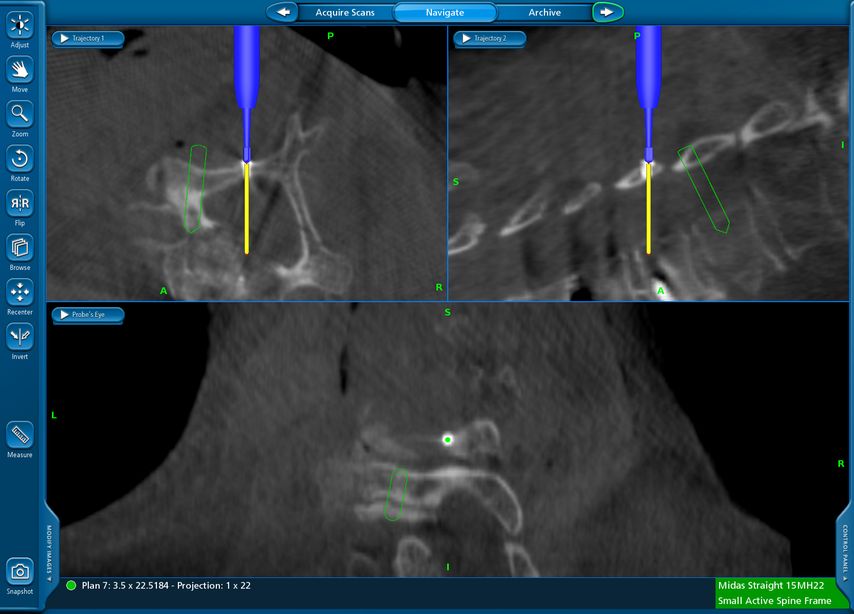

Beispiel für die Implantation zervikaler Pedikelschrauben. In diesem Fall kam es bei einem 61-jährigen Patienten 10 Jahre nach anteriorer zervikaler Diskektomie und Fusion (ACDF) C4/5 und ventraler Verplattung C4–6 zu einer Ankylosierung auch von C6/7. Nach Sturz kam es zu einer Fraktur bei C6/7 mit begleitender Bogenfraktur und auch Beteiligung der dorsalen Ligamenta (Abb. 1 und 2). Klinisch bestanden ausgeprägte Nackenschmerzen und kein neurologisches Defizit. Es wurde die Indikation der dorsalen Verschraubung von C4 auf Th1 gestellt. Intraoperativ wurde routinemäßig zusätzlich eine kleine Referenzschraube in einer Lamina – entfernt von der Dornfortsatz-Referenzklemme für die Navigation – gesetzt. Mit dieser konnte intraoperativ die Genauigkeit der Navigation exakt überprüft werden (Abb. 4 und 5). Mittels navigierter High-Speed-Fräse wurden die Schraubenkanäle vorgebohrt (Abb. 6), im Anschluss wurde der Bohrkanal ausgetastet und die Schrauben wurden implantiert. Abbildung 7 zeigt eine Röntgenkontrolle 3 Monate postoperativ.

Abb. 4: Screenshot der Navigationssoftware intraoperativ (Stealth Station S7). Es erfolgt die intraoperative Verifizierung der Navigationsgenauigkeit mittels kleiner Schraube in der Lamina, positioniert idealerweise entfernt von der Dornfortsatz-Referenzklemme. Die navigierte Fräse wird im Situs exakt auf die Schraubenmitte gerichtet, und die Navigation bestätigt die Genauigkeit | |